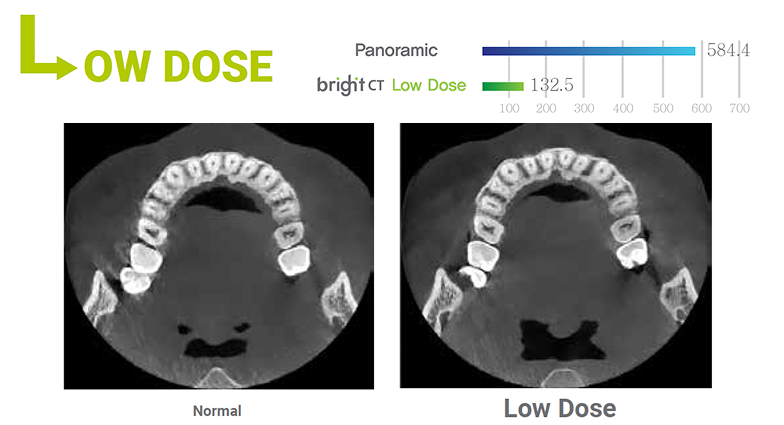

Through advanced engineering, a Dose Reduction Mode optimizes the intensity of the X-rays which lowers exposure for easily penetrated tissues.